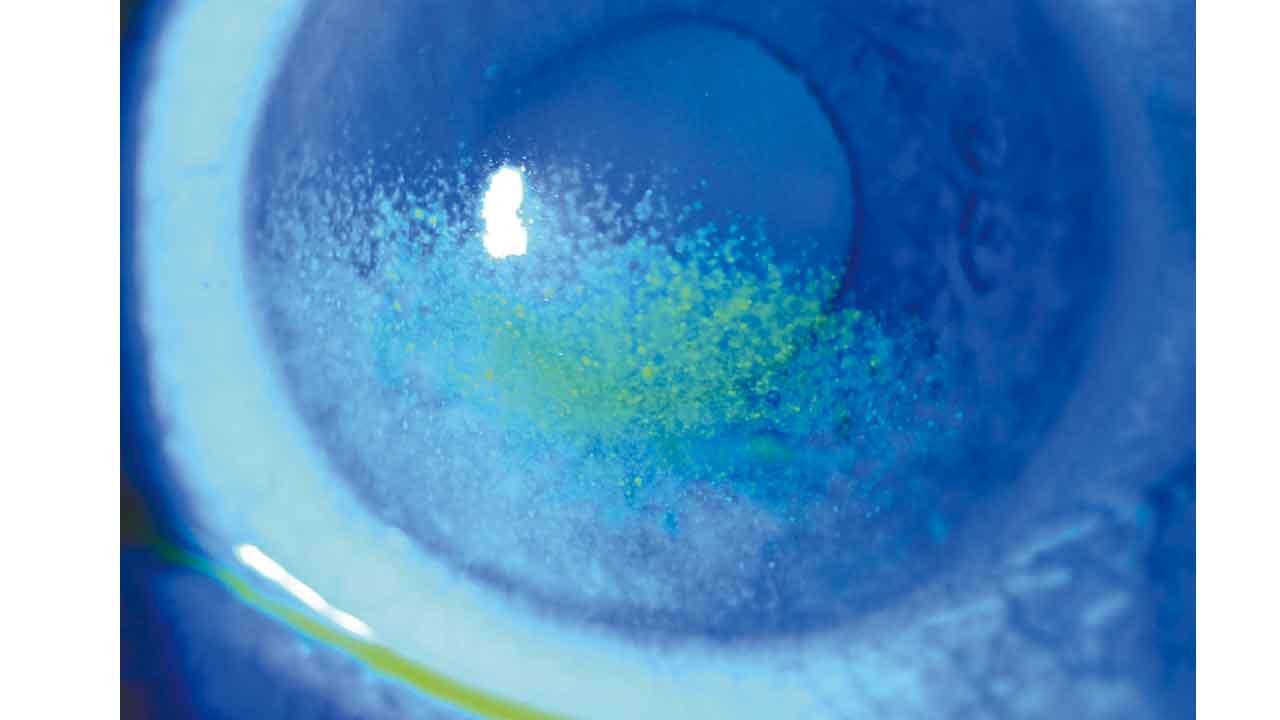

潤喉片(喉糖Lozenge)的藥物大多用於口腔或喉嚨,例如是舒緩喉嚨不適的消炎藥,通常味道帶甜;病人可把藥片放在口腔透過吸吮來溶解藥物。至於口溶片(Orally disintegrating tablet)則可以在口腔裡快速溶解,不需和水送服,方便有吞嚥困難的病人。此外,口溶片亦適用於需要迅速起效的藥物,如偏頭痛止痛藥等。